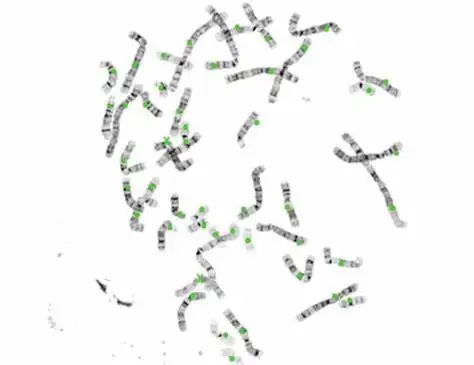

SH Chromosome Auto Karyotyping Image System

- Category:

- Supplier: Guangzhou,Shihai,Medical,Equipment,Co.,Ltd. [Guangdong,China]Guangzhou,Ltd.

RUB 7,688.10

In Stock